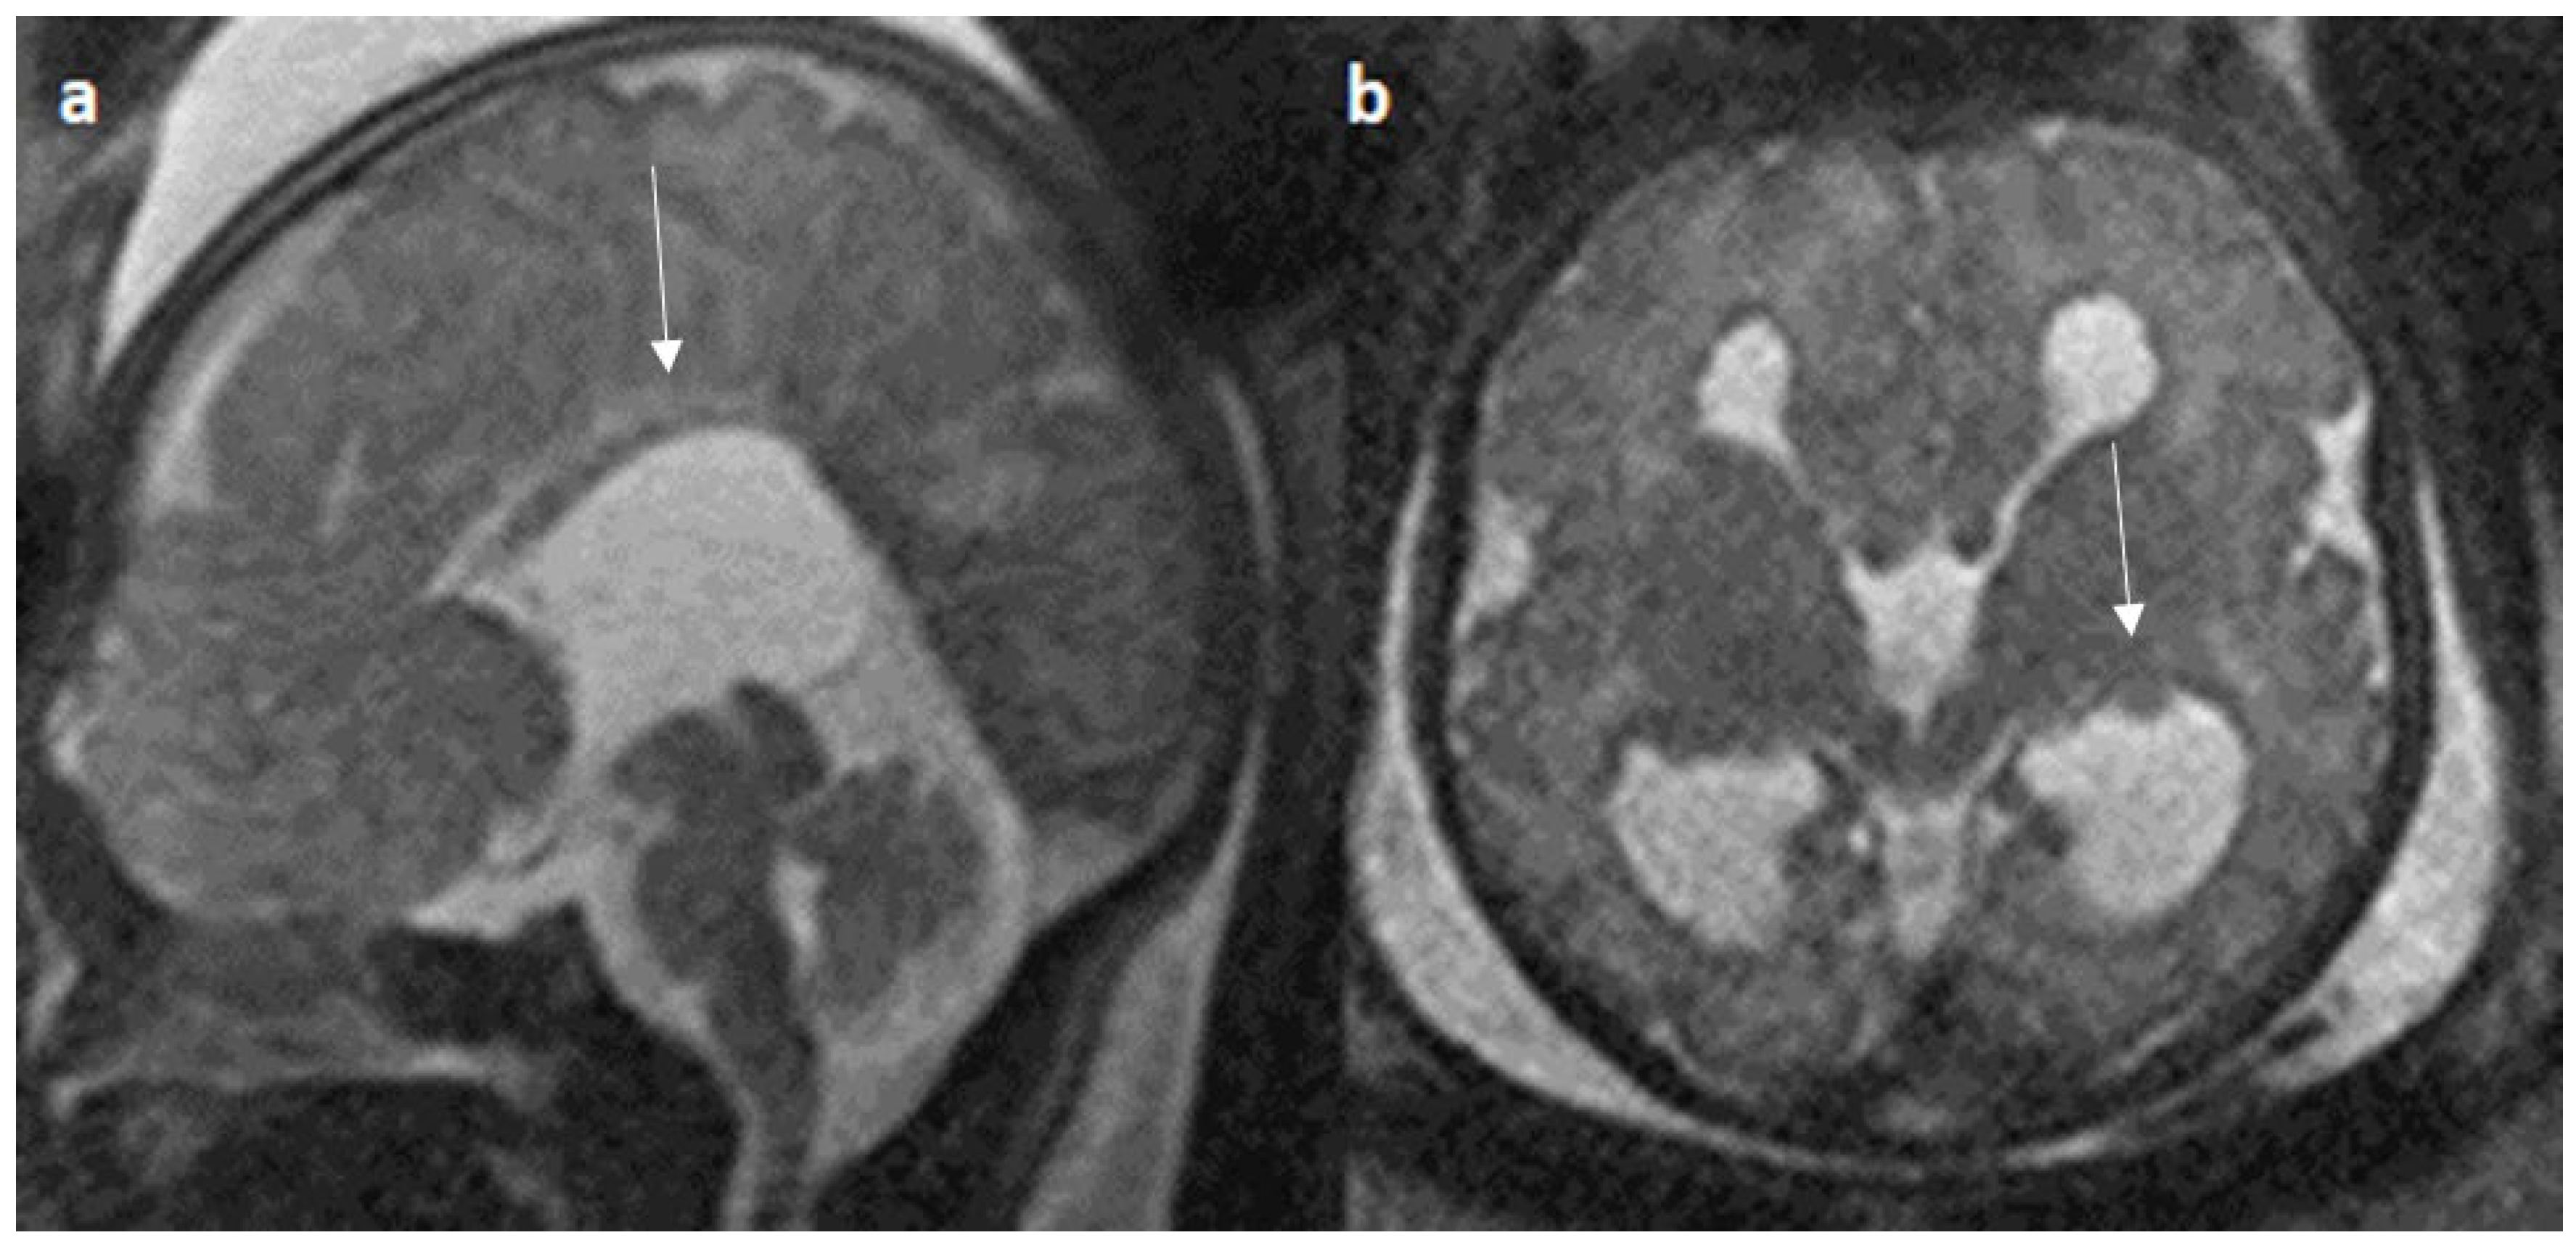

Colpocephaly is seen in 13/24 cases (54%) (Figure 5). Of them, 12 cases had complete agenesis, and one case had hypoplasia. Absent septum pellucidum is seen in 5/24 cases (20.8%) (Figure 6); 4 cases had complete agenesis, and one case had hypoplasia. Probst bundles are identified only in the isolated form of CCA and account for 3/19 cases (15.7%) of complete agenesis and 3/4 cases of the isolated form of CCA (Figure 7). Probst bundles are not seen in other subclasses of CCA. Ventriculomegaly is seen in 7/24 cases with an incidence rate of 0.29%, 5 cases had complete agenesis, and 1 case each had hypoplasia and hypoplasia with dysplasia.

Figure 10.

Fetal MRI images of a 26 gestational weeks aged fetus with hypoplasia of the corpus callosum. (a) A T2-weighted sequence in mid sagittal plane image shows normal anterior part of corpus callosum with absent posterior part (arrow), suggesting hypoplasia of posterior region with anterior remnant, rest of the brain parenchyma in this section is normal. (b) A T2-weighted sequence in axial plane showing a small midline interhemispheric fluid collection/cyst without communication with the lateral ventricles.

In our study, vermian hypoplasia represented up to 10% of posterior fossa anomalies, which was less when compared to research by Manganaro et al. and Ibrahim et al. that found up to 30% of related cerebellar malformations [42,44]. Furthermore, Byrd et al. reported that 7% of cases had vermian hypoplasia [23]. 5% of our cases had the Dandy Walker variant with an abnormal and distorted medulla, which is lower than the study performed by Neal et al. and Byrd et al. [21,23]. Neural tube defects are noted in 5% of cases, which is in line with the study performed by Byrd et al. [23] and lower when compared to the study performed by Ibrahim et al. [44].